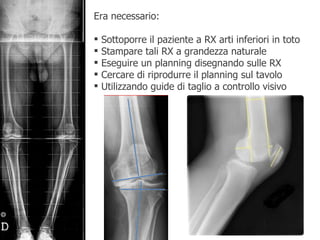

Era necessario: Sottoporre il paziente a RX arti inferiori in toto Stampare tali RX a grandezza naturale Eseguire un planning disegnando sulle RX Cercare di riprodurre il planning sul tavolo  Utilizzando guide di taglio a controllo visivo

Il planning

Se sul planning programmavo una determinata resezione, sul campo misuravo ed eseguivo tale resezione con possibili errori legati a fattori diversi